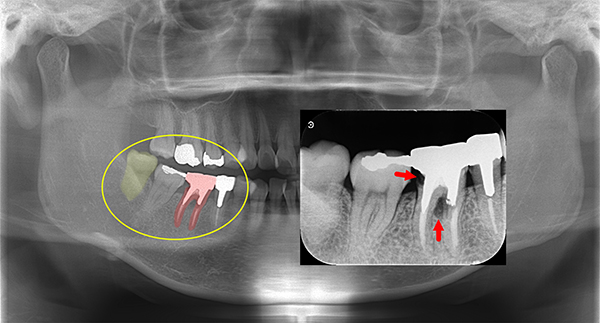

写真で見る、顕微鏡を用いた根の治療

お口の中は通常この様に暗く、目視だとなかなか細部までは見えません。

特に歯の根っこはとても複雑になっていているため、目視のみの治療には限界があります。 -

当院では顕微鏡を用いて上記のサイズに拡大して、細かい歯の根っこの治療を行いますので、神経を傷つけずに、リスクの少ない治療を心がけております。

上記は歯のレントゲン写真です。二本足のように、歯が歯茎に埋まってますが、右の歯の黒い部分(二本足のつけ根の部分)が菌に冒されてます。

-

非常に細かい部分ですが、顕微鏡を使い、菌に犯されているところを治療した後にレントゲンを取りました。

しっかり治ってます!!